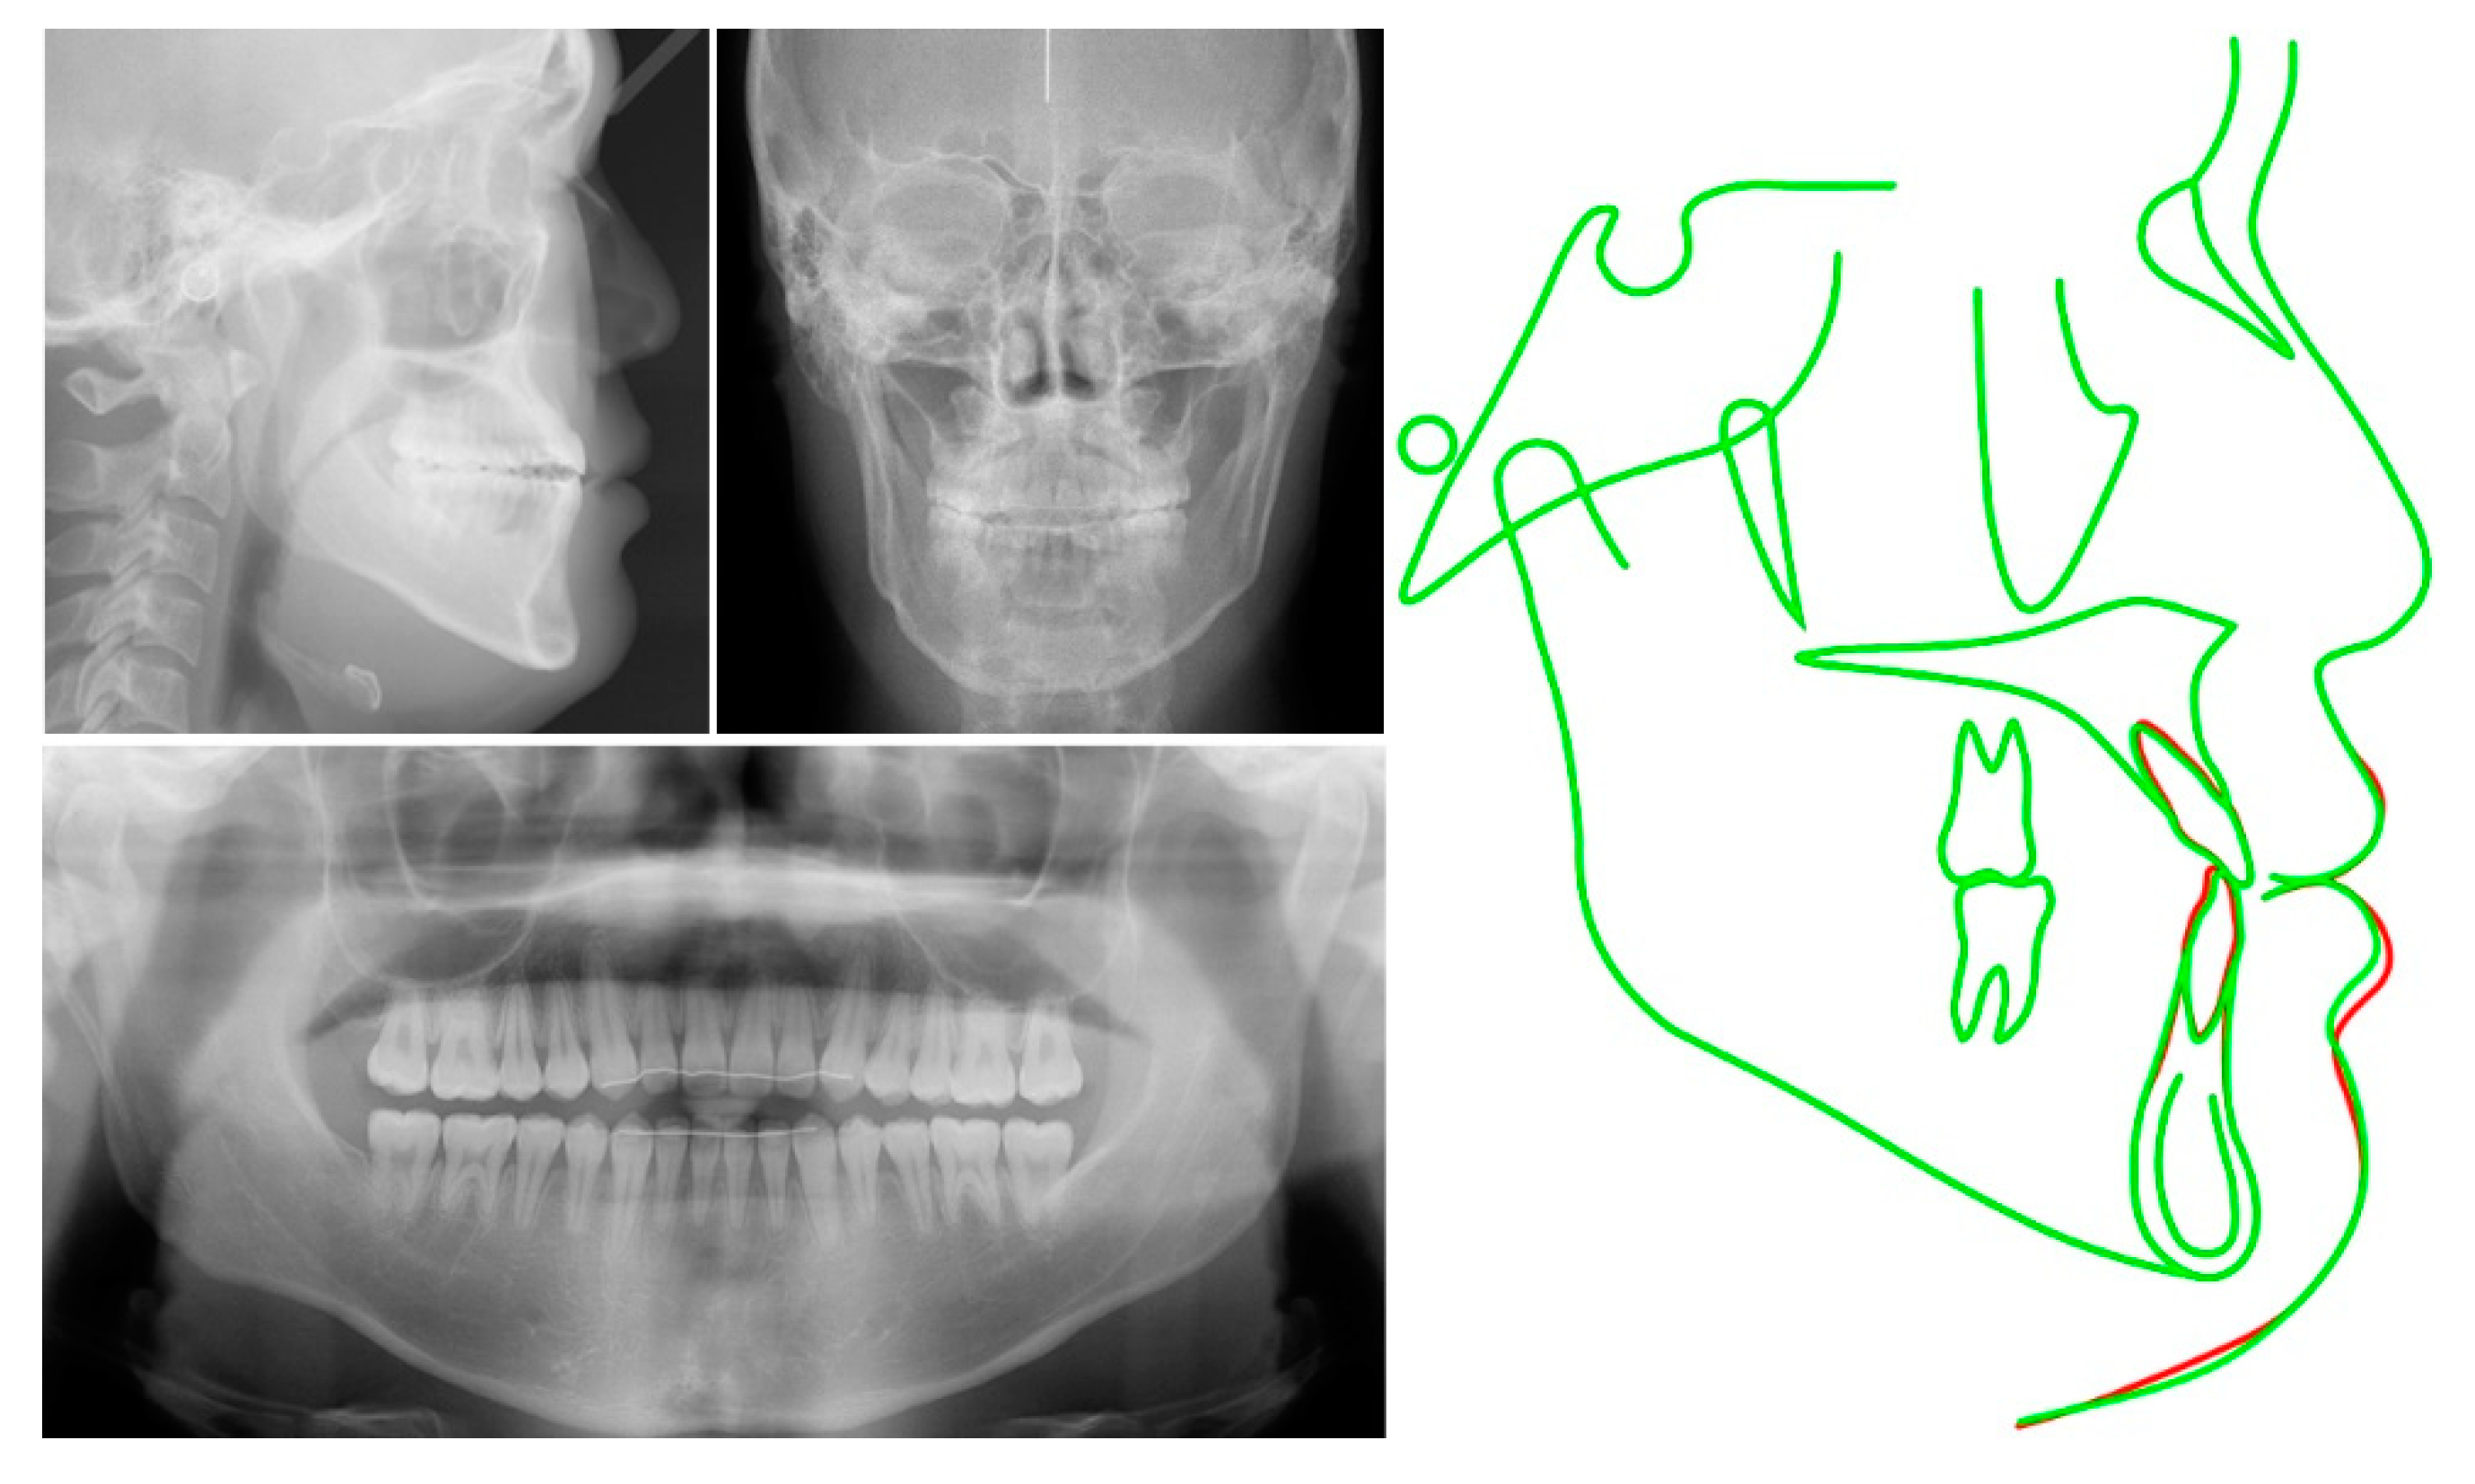

2. Case Report

2.1. Diagnosis and Etiology